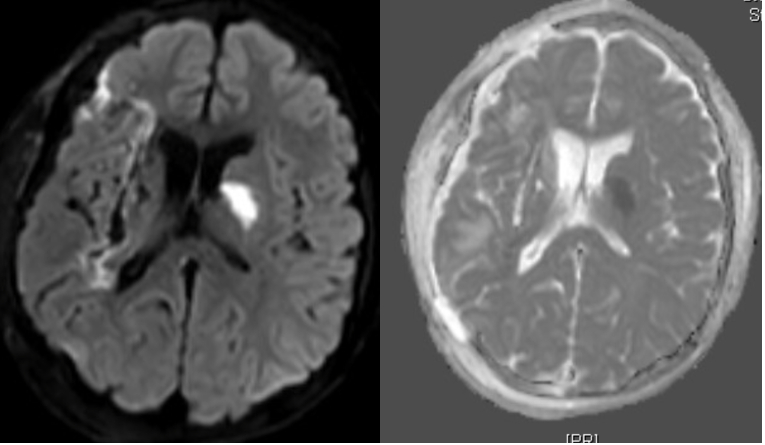

Case Summary: In less than 400 words, please summarize the case. Briefly describe the case and any particular complexities and/or complications encountered.: An 18-year-old male with past medical history of right basal ganglia (BG) intracranial hemorrhage (ICH) at age 6, hypertension, seizures, recurrent gastrointestinal (GI) bleeds, G-tube dependent, subdural hygroma requiring multiple pseudomeningocele taps, developed an episode of slurring of words, worsening left sided weakness, and unresponsiveness at the age of 17 years 6 months. CT head showed recurrent bleed in right BG and was taken for hemicraniectomy and evacuation. A subsequent MRI Brain revealed a left BG infarct.

DSA showed no AVM but presence of microaneurysm at left distal lenticulostriate artery and dissecting aneurysm at left calcarine artery. The patient was discharged to acute rehabilitation. MRA brain completed 3 months later showed multiple hemorrhagic foci in the brain parenchyma and old lacunar infarcts in the deep gray and white matter, concerning for a genetic etiology.